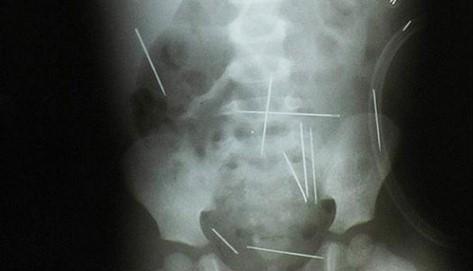

Em dezembro de 2009 a equipe médica do Hospital do Oeste, em Barreiras, Bahia, coordenada pelo diretor Luiz César Soltoski, descobriu quarenta e duas agulhas espalhadas pelo corpo dum menino de dois anos. Duas perfuraram o pulmão, uma entrou no fígado, outras fincaram na garganta, barriga, pernas, etc. Ele foi tratado como um verdadeiro boneco de feitiço.

O fato foi relatado à Polícia Civil que deu início às investigações. A mãe do menor, residente em Ibotirama, Bahia, informou que o garoto apresentava comportamento estranho e ficava nervoso sempre que o padrasto o convidava para sair. O próprio padrasto, Carlos Magalhães, 30 anos, auxiliar de serviços gerais, confessou que o menino era levado à casa de uma mulher chamada Angelina que praticava rituais de magia negra. Segundo o depoimento registrado pela escrivã da delegacia de Ibotirama, Angelina teria pedido diversas vezes para que o padrasto inserisse as agulhas no menino.

Detalhe duma chapa de radiografia do menino tirada dia 09/12/2009, no Hospital do Oeste, em Barreiras, mostrando algumas agulhas de costura inseridas em eu corpo durante rituais de magia.[34]

Este menino sobreviveu bastante lesionado, assim como alguns sapos sobrevivem para definhar dolorosa e lentamente em certos rituais. O caso tomou os noticiários jornalísticos da semana – sobretudo porque, de acordo com a polícia, todos teriam “envolvimento com uma seita religiosa”.[35] – Três pessoas foram presas preventivamente: A dona do centro, o padrasto e sua amante que teria sugerido que ele levasse a criança àquele lugar.